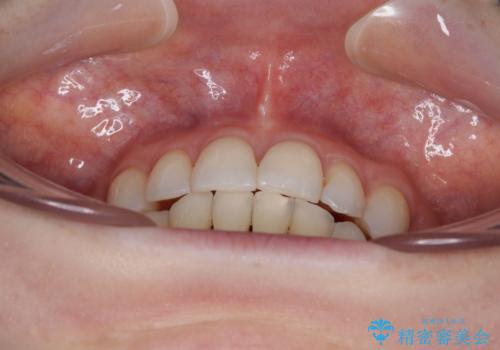

- 八重歯や前歯のデコボコを気にして来院された患者様です。

骨格的な左右差と、歯列から外れている歯が上下で左右非対称になっていることから、上下正中が歯1本分ずれている状態でした。

八重歯の改善と、上下の正中位置を極力合わせていくことを目的として、上下左右の第一小臼歯4本を抜歯し、ワイヤー装置にて矯正治療を行うこととしました。

アンカースクリューを用いて正中位置を調整したことで、上下の正中位置をほぼ一致させることができました。

移動量が多かったため、治療期間は長くなりましたが、大変満足のいく仕上がりとなりました。